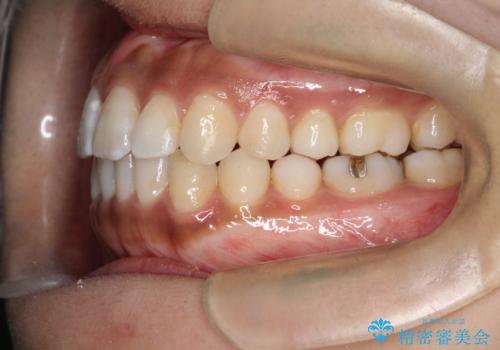

インビザラインと補助装置の併用による八重歯の抜歯矯正

- 八重歯を治したいとのことで来院されました。

重なりが強い右側の上下の歯を1本ずつ抜歯する計画としました。

インビザラインでの治療がご希望でしたが、右上の歯のかさなりが強いところは、補助装置である程度動かしてからインビザラインに移行することにしました。

下顎はインビザラインのみで治療を行いました。